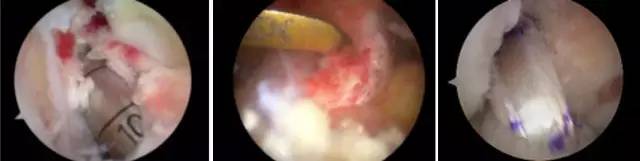

开展关节镜下交叉韧带单、双股解剖重建技术、膝关节多韧带损伤的一期修复重建术、半月板缝合技术、骨软骨移植技术、同种异体移植治疗交叉韧带损伤、双隧道重建交叉韧带、肩关节镜下肩袖修补和SLAP损伤修补术,及肘、踝、腕、髋关节镜术。专业运动员伤病诊治技术、股骨髋臼撞击综合症、股骨头坏死阶梯治疗技术、骨软骨移植技术。

关节镜清理、软骨移植修复

膝关节镜/肩关节镜/踝关节镜/髋关节镜/肘关节镜